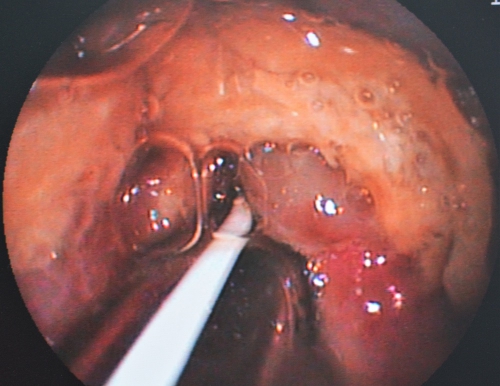

下の写真をご覧になってみてください。この写真は食道の下流域、胸部食道から胃の入り口である噴門部(中央部のすぼまっているところ)を見ている内視鏡の画像です。

実はこの写真は胸部食道に詰まった異物を摘出した後のものです。異物は「牛皮のガム」でした。この写真は閉塞が起きてから、半日程度経過したところで内視鏡検査を行ったものです。

この画像は食道が圧迫に対していかに弱い臓器なのかを示す画像としてご覧ください。

下の写真で黄色矢印の先がへこんで周囲の粘膜が出血しています、中央部は「牛皮の尖った部分」に圧迫されて潰瘍を作っており、食道穿孔の危険性がありました。

また、緑矢印の先に広い範囲で赤黒く粘膜面の変色が見られます、こちらも圧迫によって粘膜面にうっ血が生じており、食道粘膜にダメージを起こしているのが分かります。